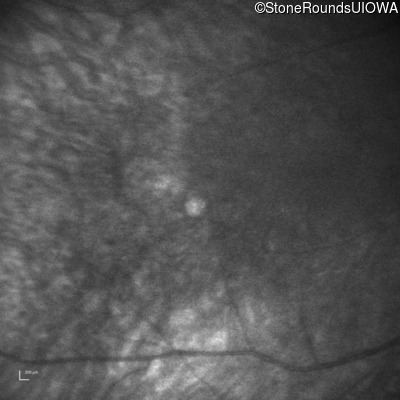

Infrared Fundus Photograph - Right -

No Light Perception

Exemplar

Expanded OCT Stack

×